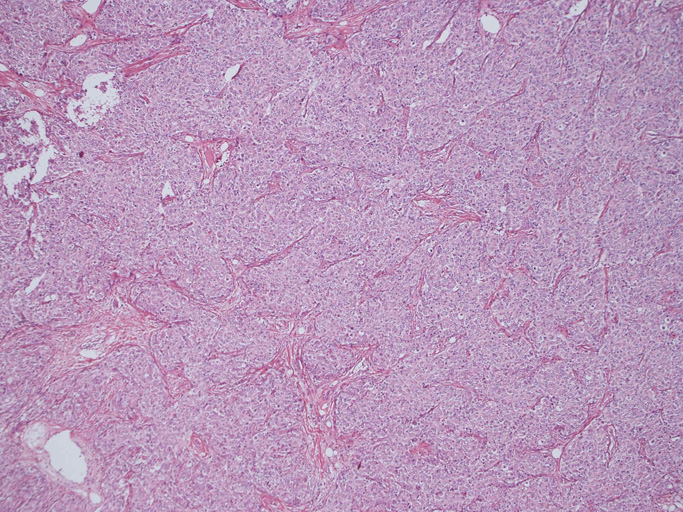

30歳代男性/ 大網腫瘍

上腹部圧迫感で受診. 画像所見で大網に13x11cmの腫瘤を認める。腫瘍摘出および膵脾合併切除術が行われる。腫瘍本体は網嚢内に位置. daughter lesionが複数認められた。膵脾には浸潤なし。リンパ節転移あり。6ヶ月後に腹膜播種で再発。

腫瘍は, 細血管を含む細い線維組織束で分画された胞巣状充実性病変で(Fig01),類円形ないし卵円形のvesicularな核をもつ円形, 多稜形の細胞が増殖している。核小体は小型, やや不明瞭。細胞質は境界が不鮮明で好酸性泡沫状を呈するものが多い。大型核やbizzarreな核の出現も認められる(Fig02-05)。血管周囲にリンパ球浸潤が認められる部分がある(Fig06,07)。